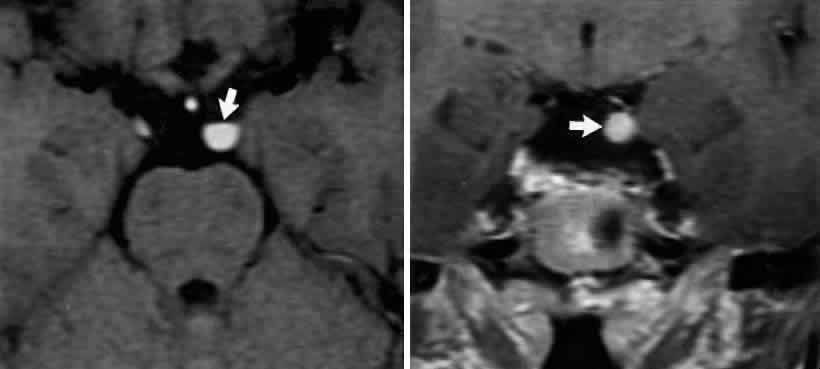

In the cavernous sinus, the abducens nerve may be involved in combination with the ophthalmic-trigeminal, third, or fourth nerves. Abducens monoparesis is frequent with cavernous sinus lesions, perhaps related to the nerve's location within the sinus, inferolateral to the carotid artery and unsupported by the dural wall of the sinus.19,20 Isolated abducens palsy occurs with carotid-cavernous fistulas (especially with spontaneous dural shunts21) and intracavernous aneurysms20 (Fig. 7), and is the earliest indication of contralateral spread of cavernous sinus thrombosis. Sixth nerve palsy accompanied only by ipsilateral Horner's syndrome also points to the cavernous sinus, since the ocular sympathetics from the carotid plexus may be simultaneously involved.22

Fig. 7. A. Chronic isolated sixth nerve palsy. B. Coronal and Axial (C) MRI sections showing large intracavernous internal carotid aneurysm (arrows).